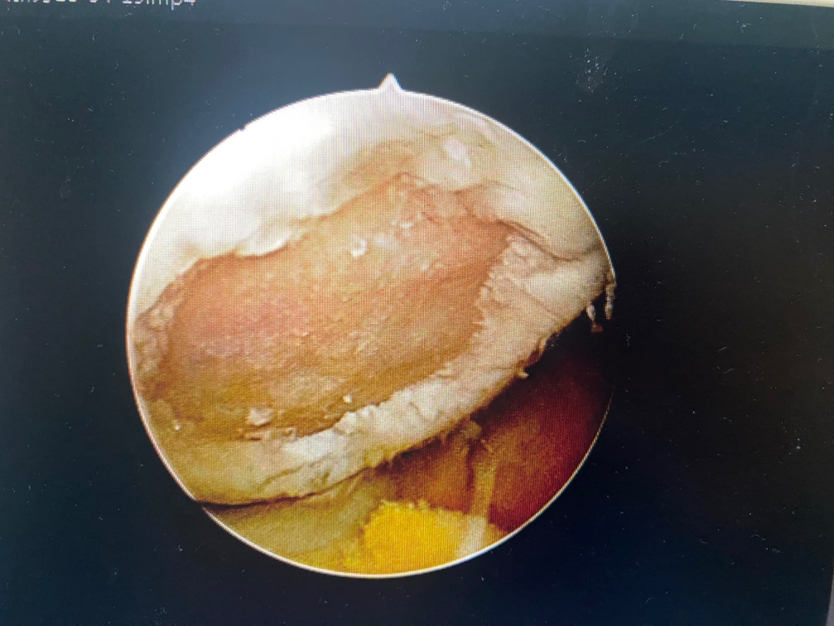

1展示关节镜微创技术:凝胶修复软骨损伤(髌骨软骨损伤凝胶支架修复)

滑车软骨损伤 (软骨剥脱,软骨下骨暴露)

清理微骨折处理

微骨折后骨髓骨细胞溢出

注射凝胶支架覆盖软骨损伤区

软骨修复后(完全覆盖填充)